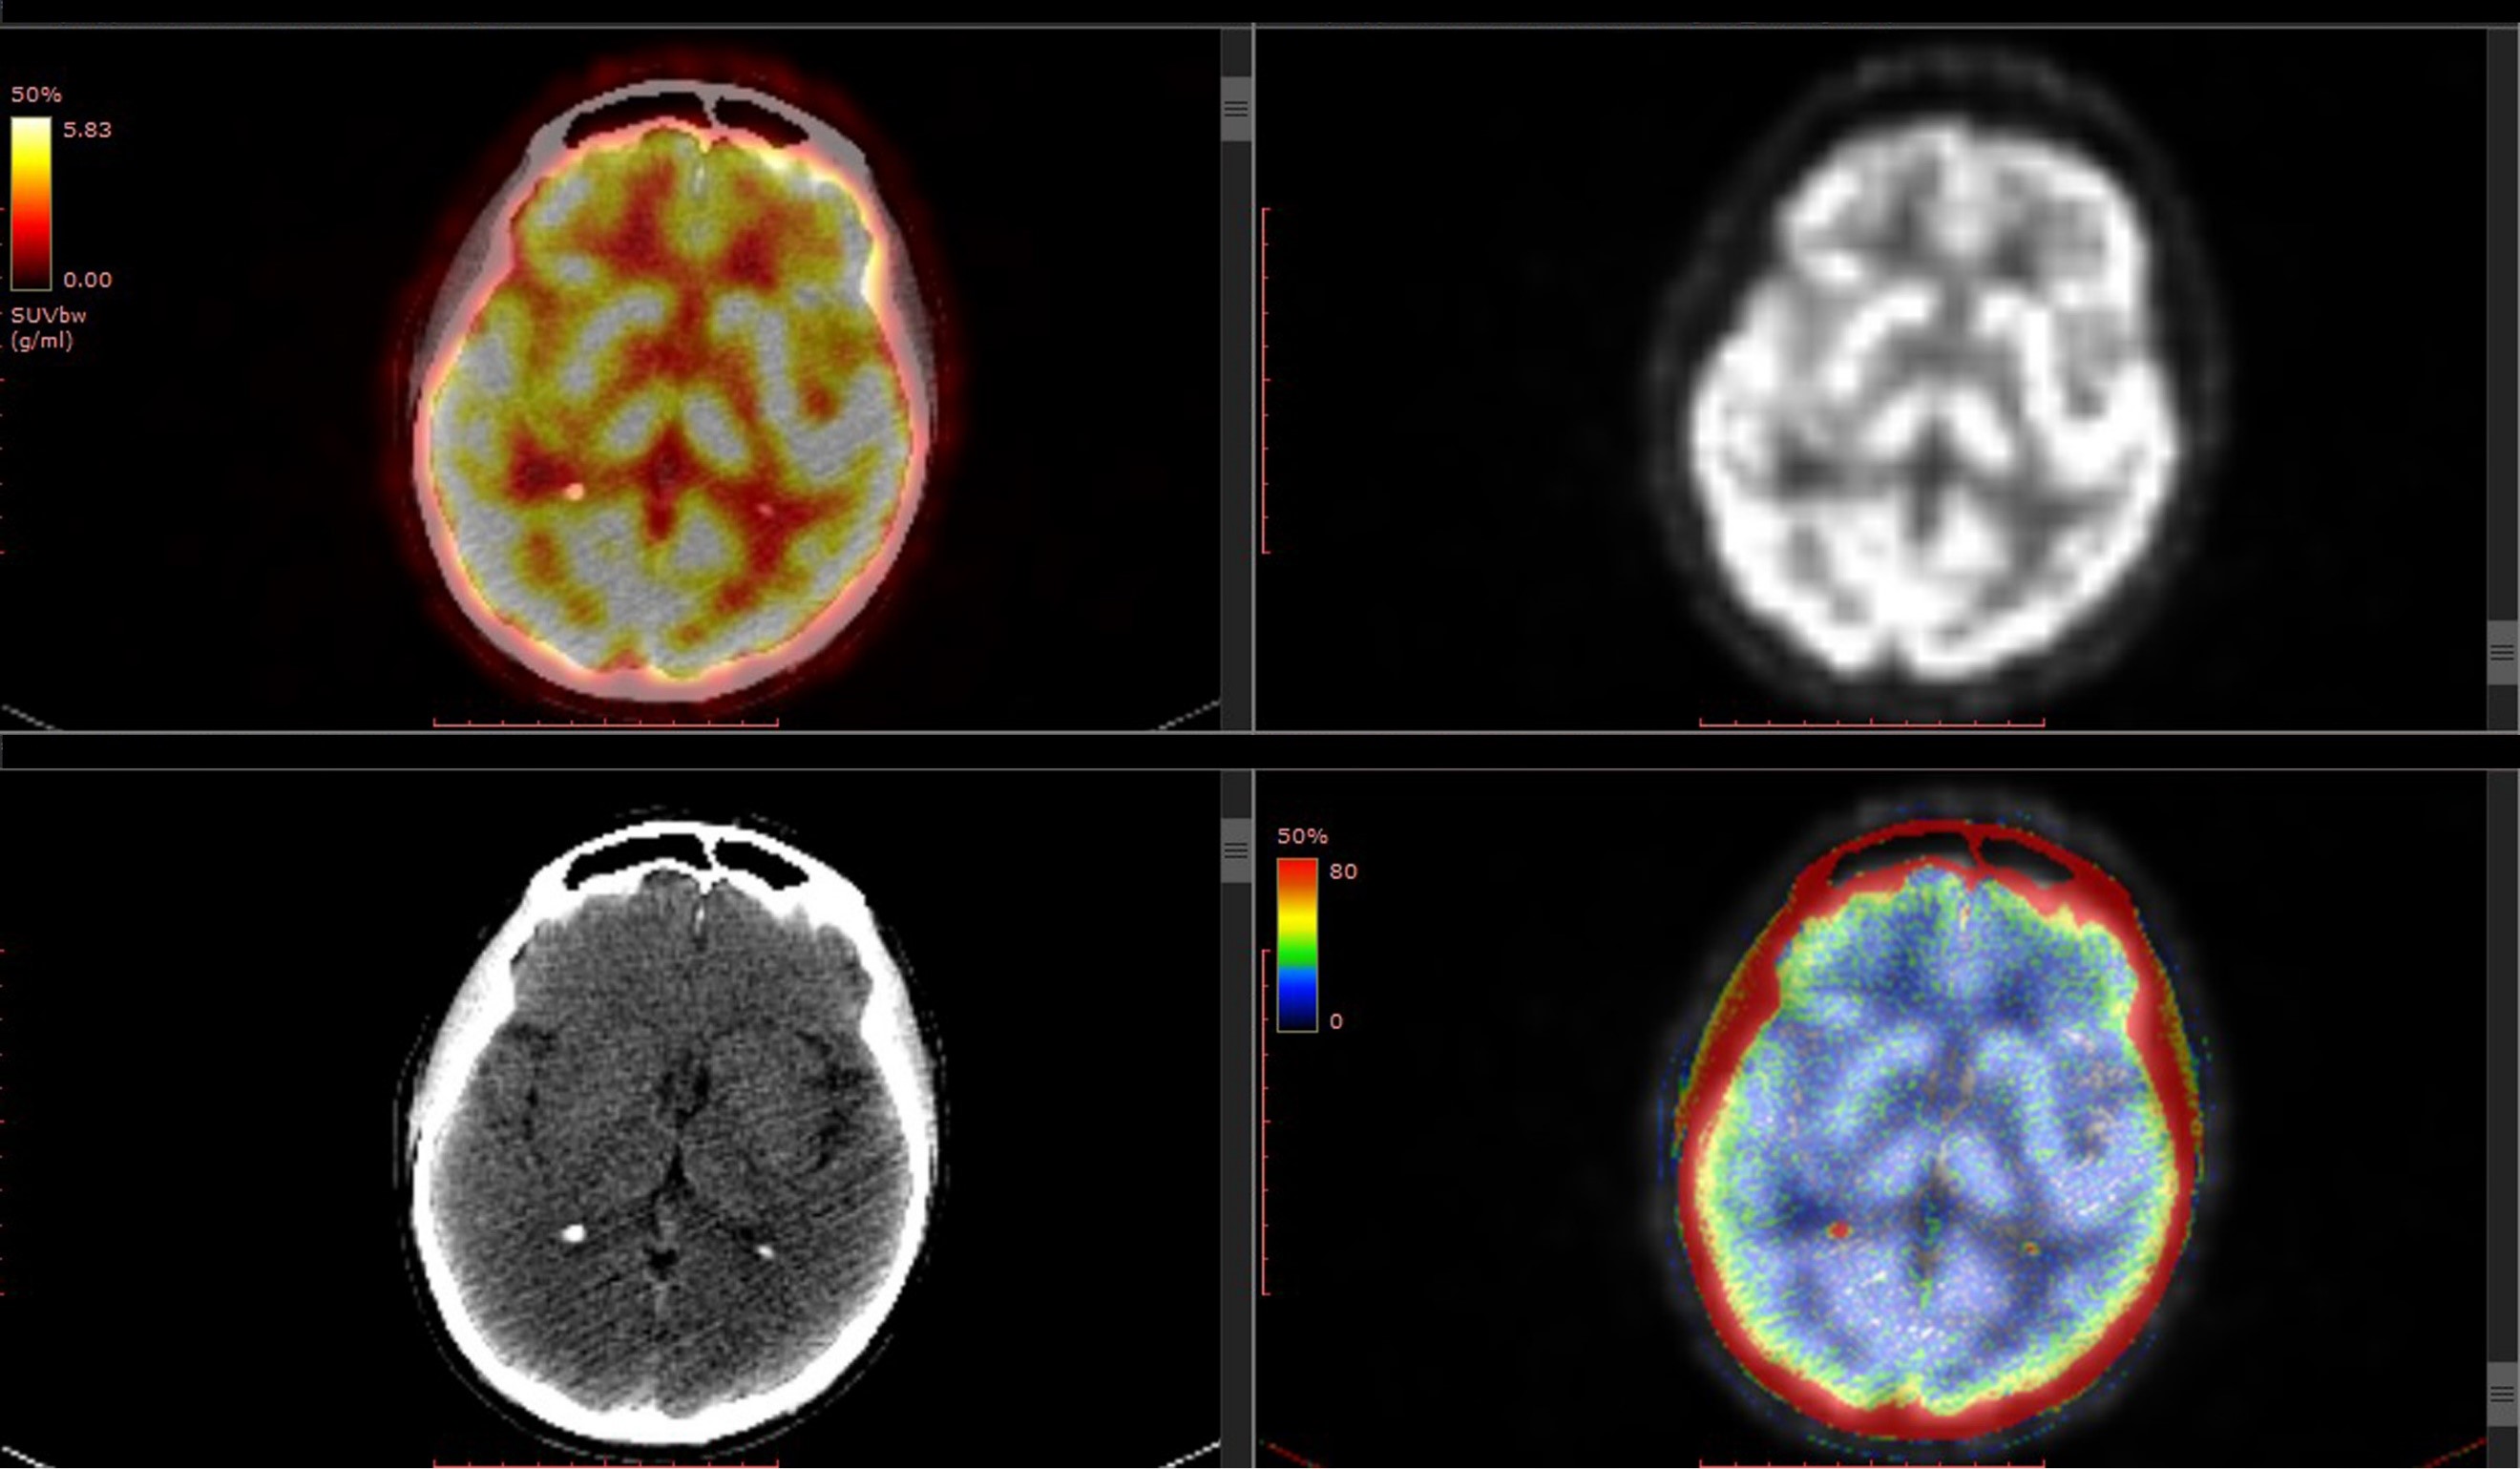

神经导航(DTI、MEG等)、术中磁共振等辅助定位设备的应用,降低术中解剖结构辨认的难度;机器人辅助、神经内镜辅助,对于深在解剖位置操作的帮助很大。目前已成功欧美兴起的激光间质热疗(LITT),已成为颞叶内侧型癫痫的主要治疗手段之一,其临床应用范围还将进一步拓宽。激光间质热疗(LITT)可以在MR引导下完成操作,实现准确定位、实时监护,且其使用激光探头,探头外面有冷却系统,使用生理盐水降温,可以设置好温度以保护重要组织。

激光间质热疗(LITT)可以很好的控制所需温度和毁损的范围,其温度设置在40度以下一般不会毁损,80度以上是立即毁损,60-80度通过时间来控制毁损程度。激光间质热疗(LITT)相对于放射治疗,更准确合适,并发症更少。国际三大儿童医院之一加拿大多伦多儿童医院SickKids神经外科主席James T. Rutka教授在小儿癫痫的LITT治疗方面尤为擅长,Rutka教授及其带领的团队,对儿童癫痫的外科手术治疗LITT等方面积累了诸多经验,发表了许多著作。